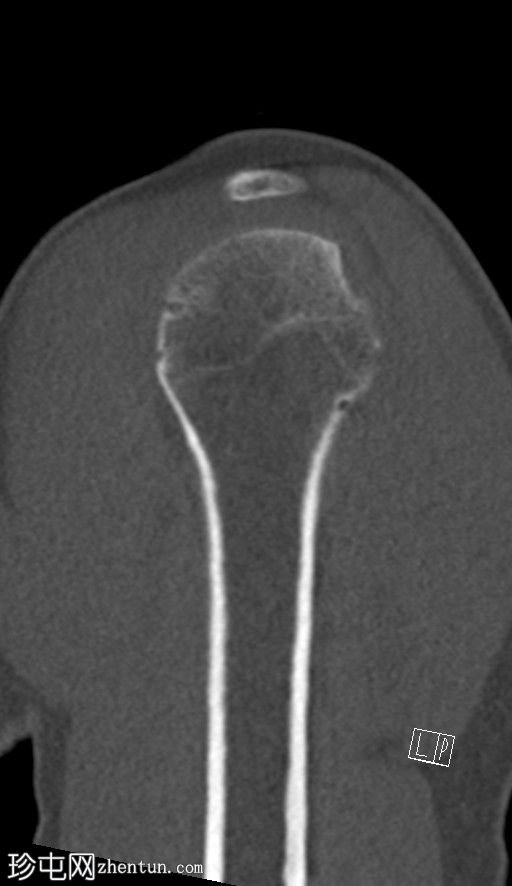

矢状位

非增强

CT显示肱骨头后外侧缘存在缺损及骨碎片,提示Hill-Sachs损伤。

右侧肩胛盂前下缘可见一小块骨碎片,提示Bankart损伤。